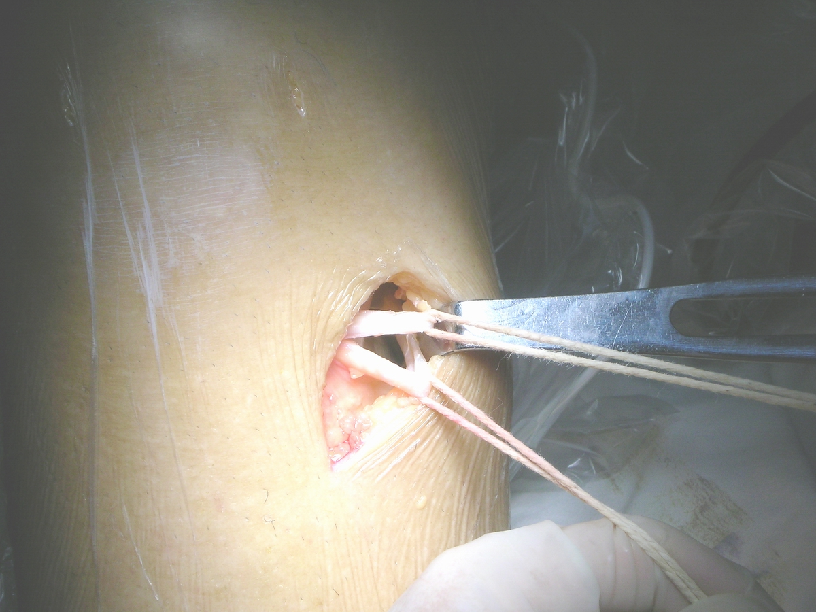

取材

髌腱中三分之一

最好使用摆锯,避免垂直于软骨面敲击,防止损伤髌骨软骨

也有使用环钻取腱的

髌腱修整

测量套管:

Ø=7,8,9,10,11,12 mm

套管内径=钻头直径=髌腱标本直径

修整 后骨—腱—骨复合体:

1.毫无阻碍地顺利通过所选用的测量套管

2.骨端应修整得稍圆滑,以利于进入骨隧道

3.两端穿线,用于引导牵引用

拉进移植物

界面螺钉固定移植物

上胫骨端界面螺钉

拉紧B-P-B,并行后抽屉试验,紧张重建韧带,上胫骨端的界面螺钉,必要时可用门型钉或普通螺丝钉加强固定。